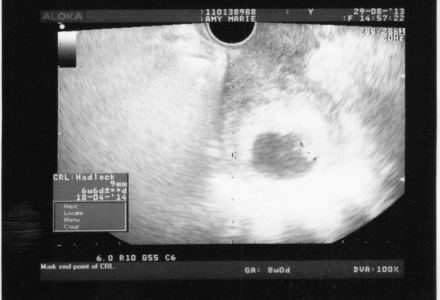

A Bun in the Oven